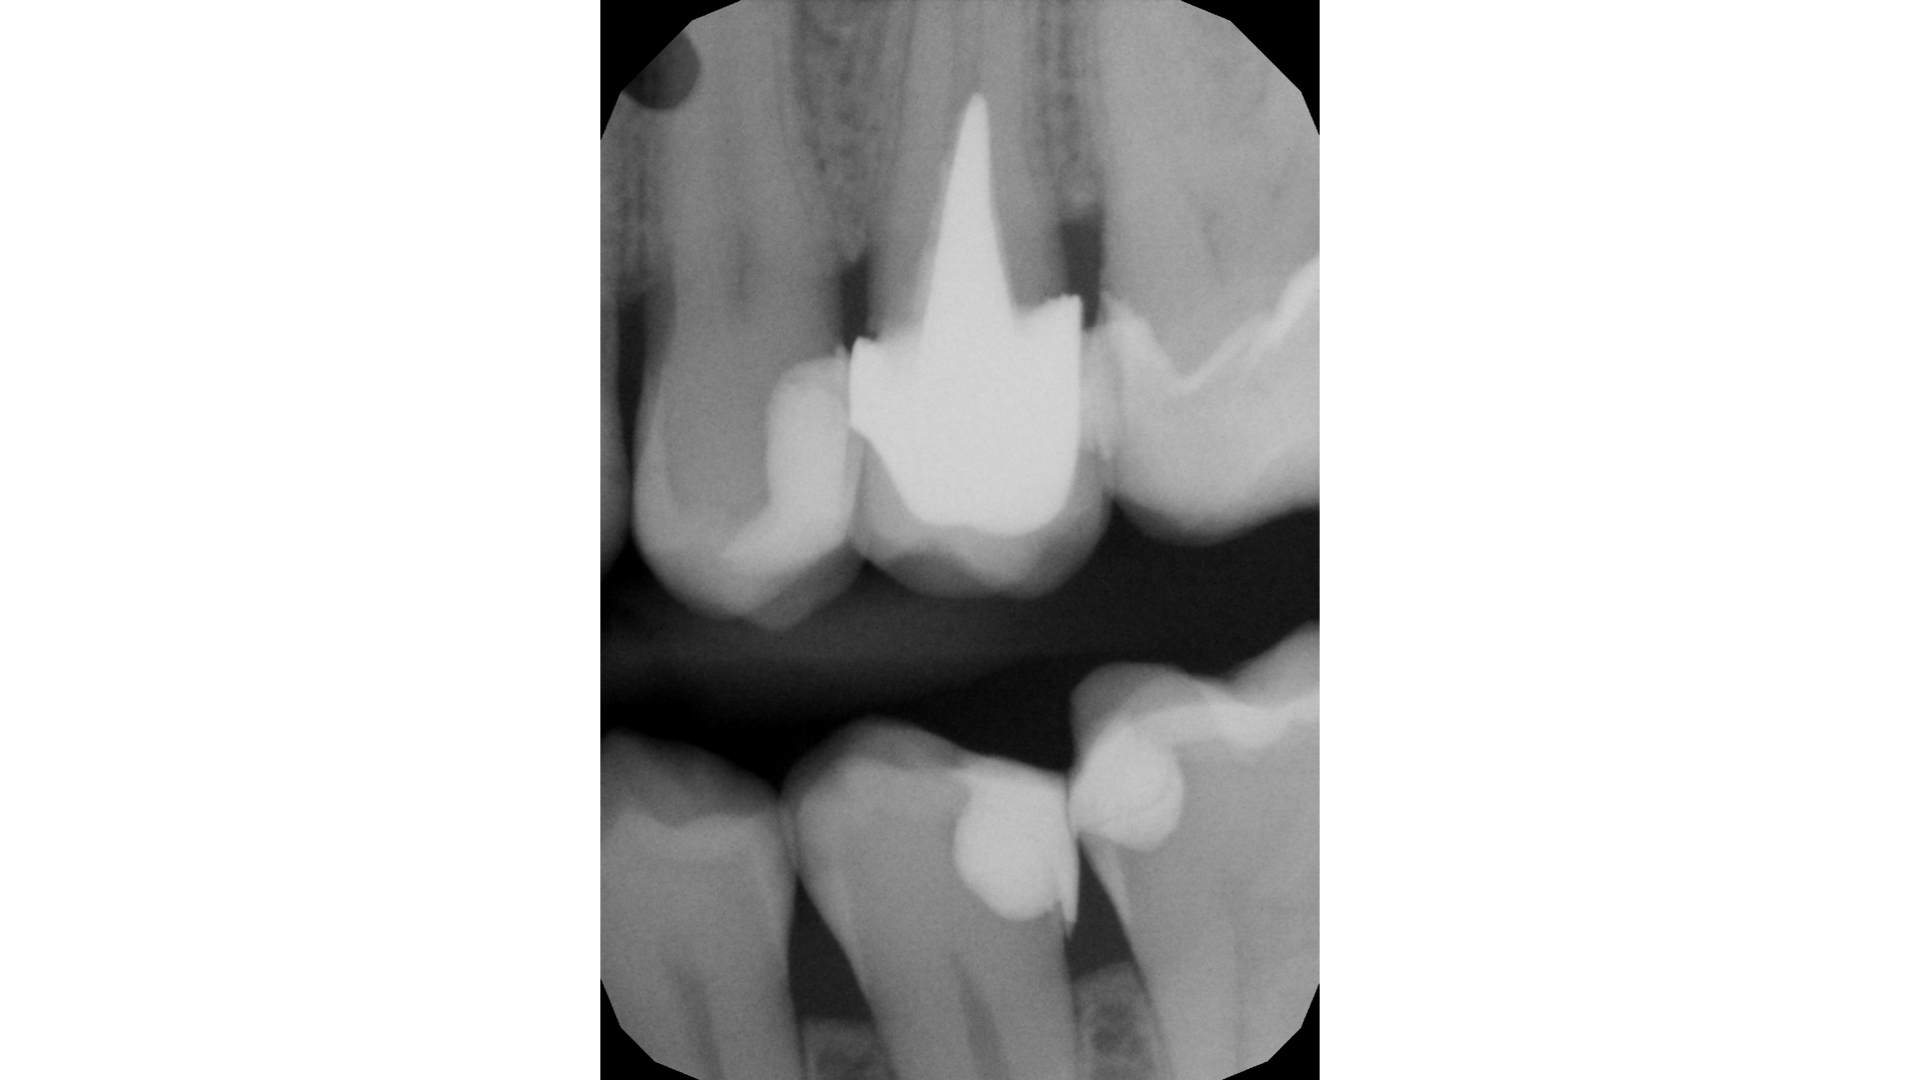

Radiografia bitewings iniziale che mostra un precedente restauro infiltrato mesiale a 2.6 ed un restauro debordante distale a 2.5Fotografia occlusale iniziale pre-opertoria

Controllo occlusale Controllo radiografico